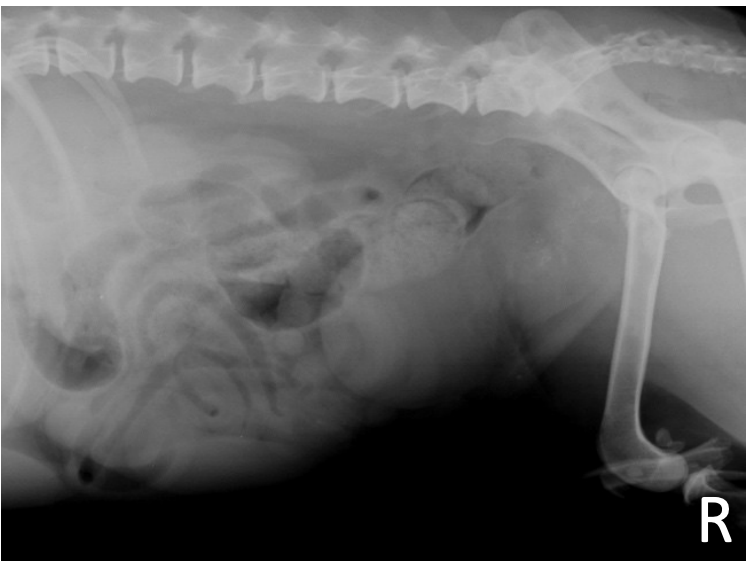

What is shown in these images?

A

normal prostate in an intact dog

-arrow heads indicate the prostate

-white line represents distance between sacral promontory and pubis

What are the characteristics of prostate size?

*varies with age, body size, repro. status, and breed

*in intact males:

-should not occupy greater than 70% of the distance between sacral promontory and pubis on lateral view

-should not occupy more than 50% of the pelvic canal on VD view